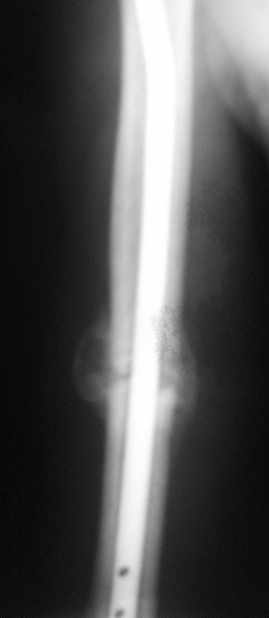

Уважаемые коллеги!Обратился пациент, оперирован не у нас.

Что делать?

Варианты:

1. Заблокировать.

2. Ничего не делать.

3. Заменить штифт на более толстый.

4. Еще варианты?

Спасибо. (Извините за снимки, дома нет негатоскопа, если необходимо - завтра пересниму).

однозначно не блокировать и не убирать - есть прекрасная мозоль и все отлично срастается. Мне плохо видно - выступает ли гвоздь проксимально ( кажется, нет, гвоздь строго в уровень с костью)?

Спасибо. А не слишком ли хороша мозоль?

Большая мозоль - здоровый организм УСПЕШНО компенсирует недостатки фиксации.

Пациент обратился с жалобой на лигатурный свищ.

Амплитуда движений 70-80% от контрлаптеральной конечности с умеренной болью в месте перелома. Наиболее болезненно - заведение руки за спину (появляется боль в области плечевого сустава). Отведение - градусов 70, далее за счет лопатки.

Обычное дело, пусть разрабатывает давно, лучше с методистом. Тут по снимкам проблем не видно. Винты вводить необязательно - если хирург знает, что делает. Например, если получился хороший press-fit из-за несоответствия формы гвоздя и канала.